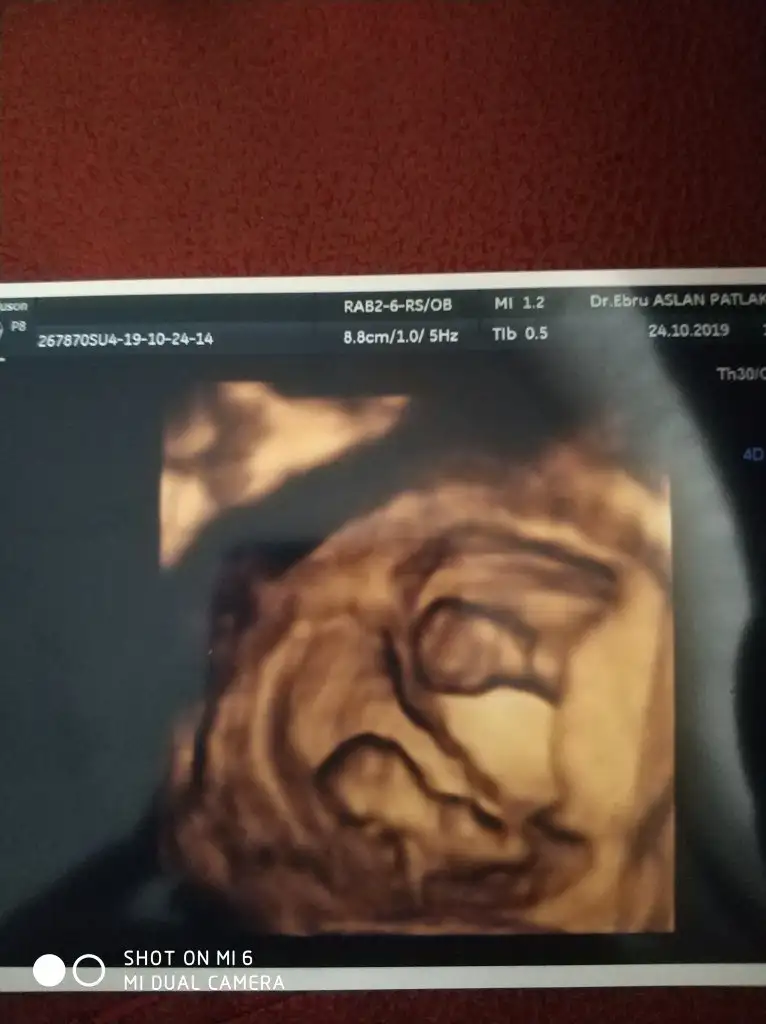

Arkadaslar bunlarda benim cift yumurta ikizlerimin 10. Hafta ultrason goruntuleri. Lutfen bana da yorum yapin![]()